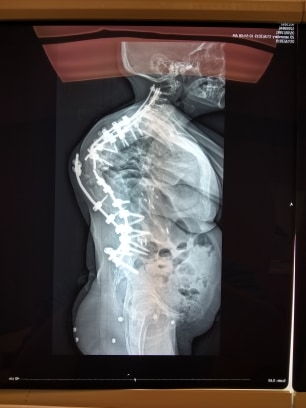

Just the tellings of life through the eyes of a 29 year old, Cajun Louisiana Native with Scoliosis, Kyphosis, EDS(Ehlers Danlos Syndrome), and other medical issues, just trying to get by. :)